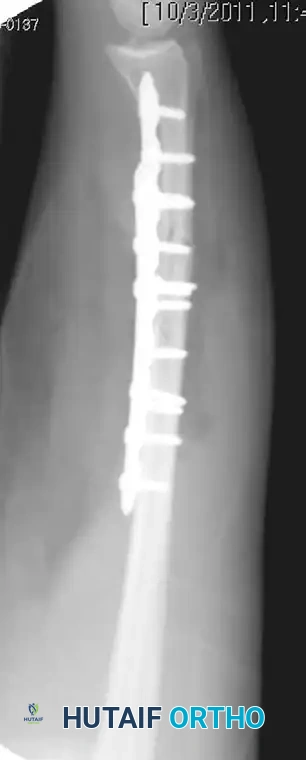

Figure 57-82A: Preoperative AP radiograph of a displaced both-bone forearm fracture in an adult.

Figure 57-82B: Preoperative lateral radiograph demonstrating significant translation and loss of the radial bow.

Figure 57-82C: Postoperative AP radiograph demonstrating anatomical reduction and rigid fixation with 3.5-mm compression plates.

Figure 57-82D: Postoperative lateral radiograph confirming restoration of alignment and appropriate plate contouring.